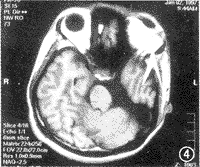

患者男,25岁,生后即发现3眼眶畸形,哭时仅见右眼及第眼有泪液,而左眼无泪,但可见粘液样分泌物。患者为第2胎,无家族史。体检:上唇外翻,左侧近正中唇裂已修补,神经系统检查为见异常。眼部检查:颜面部呈3眼外貌(图1,2)。右眼球大小无异常,呈明显水平性眼震,视力0.3(不能矫正),右眼睑及泪器未见异常。视乳头色淡、边界清楚,余未见异常。左眼无光感,睑裂4 mm×10 mm,有睫毛,上、下泪小点位置正常,左眼无眼球,仅见灰白色团块状混浊,通过眼睑可触及圆形球状物。颞侧第3眼浓后的眉毛下仅有圆形裂隙,眼睑仅2 mm×3 mm,可见睫毛,无上、下泪点,通过眼睑亦可触及圆形球状物。眼B超探查:右眼正常。左眼约17 mm×15 mm,第3眼为1.5 mm×14.0 mm,均未见明显玻璃体回声,后部未见液性暗区。眼眶X线片示右眼眶大小正常,左侧可见双眼眶,其内侧与右眼眶在同一平面约4 mm×3 mm,左眼外上方可见一小约2.5 mm×2.6 mm眼眶,双眼眶间有间隔(图3)。头颅MRI分别取横断、矢状和冠状3个截面,均行加权T1和加权T2扫描。右眼无异常,左眶内无正常眼球,仅见脂肪组织包绕一圆锥囊泡,左眼未见视神经,左视交叉及外侧膝状体亦未显示。第3只眼眶内大部分填以脂肪组织,内见少量条索状组织向后连于颞叶。左枕叶缺如,左侧侧脑室与第3脑室扩大融合,左侧丘脑与大脑脚明显萎缩,磁共振血管造影:左侧大脑后动脉仅见一小段主干,大部分分支缺如(图4~9)。脊髓MRI未见异常。1997年1月2日在局麻下行左眶内组织取出术,术中见两块肉样团块,经组织学连续切片未见眼球的任何结构,组织块以结缔组织为主,其中一块可见较发达的似为泪腺的粘液性腺,并可见完整的导管系统,在其附近尚有较集中的弥散性淋巴细胞浸润,另外一块也有类似的腺体存在,尚可见一块较大的透明软骨,发育较好(图10,11)。

图8 MRI横断面示,左诊叶缺如,枕大池与第三脑室相通

图9 MRI示左大脑后动脉分支减少